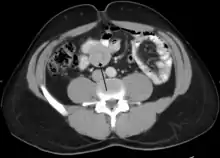

| An intussusception as seen on CT | |

An intussusception is often suspected based on history and physical exam, including observation of Dance's sign. A digital rectal examination is particularly helpful in children, as part of the intussusceptum may be felt by the finger. A definite diagnosis often requires confirmation by diagnostic imaging modalities. Ultrasound is the imaging modality of choice for diagnosis and exclusion of intussusception, due to its high accuracy and lack of radiation. The appearance of target sign (also called "doughnut sign" on a sonograph, usually around 3 cm in diameter, confirms the diagnosis. The image seen on transverse sonography or computed tomography is that of a doughnut shape, created by the hyperechoic central core of bowel and mesentery surrounded by the hypoechoic outer edematous bowel.[11] In longitudinal imaging, intussusception resembles a sandwich.[11] It is also called "pseudokidney" sign because hyperechoic tubular centre is covered by a hypoechoic rim producing a kidney-like appearance.[12]